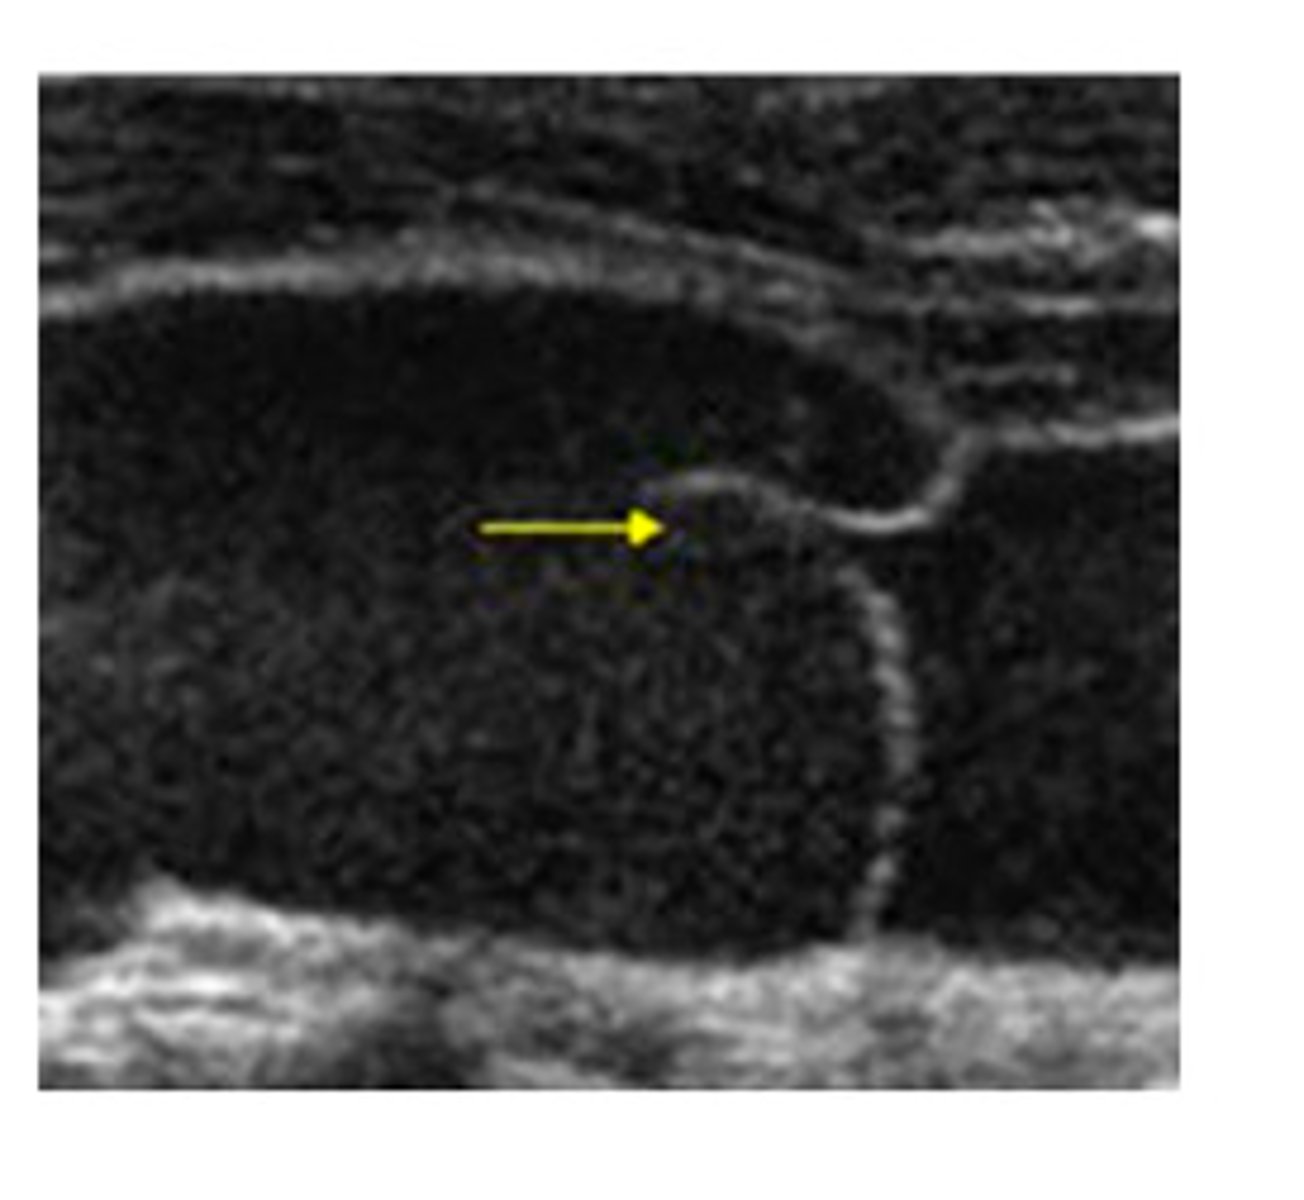

To which part of the respiratory cycle is the yellow arrow pointing in the spectral Doppler image of the lower extremity vein?

inspiration

expiration

From the appearance of the vessel in this image, is this an artery or a vein?

artery

vein

The yellow arrow is pointing to which of the following:

septation

tumor

valve

muscle

A normal vein is which of the following?

non-compressible

compressible with light transducer pressure

compressible only with Valsalva